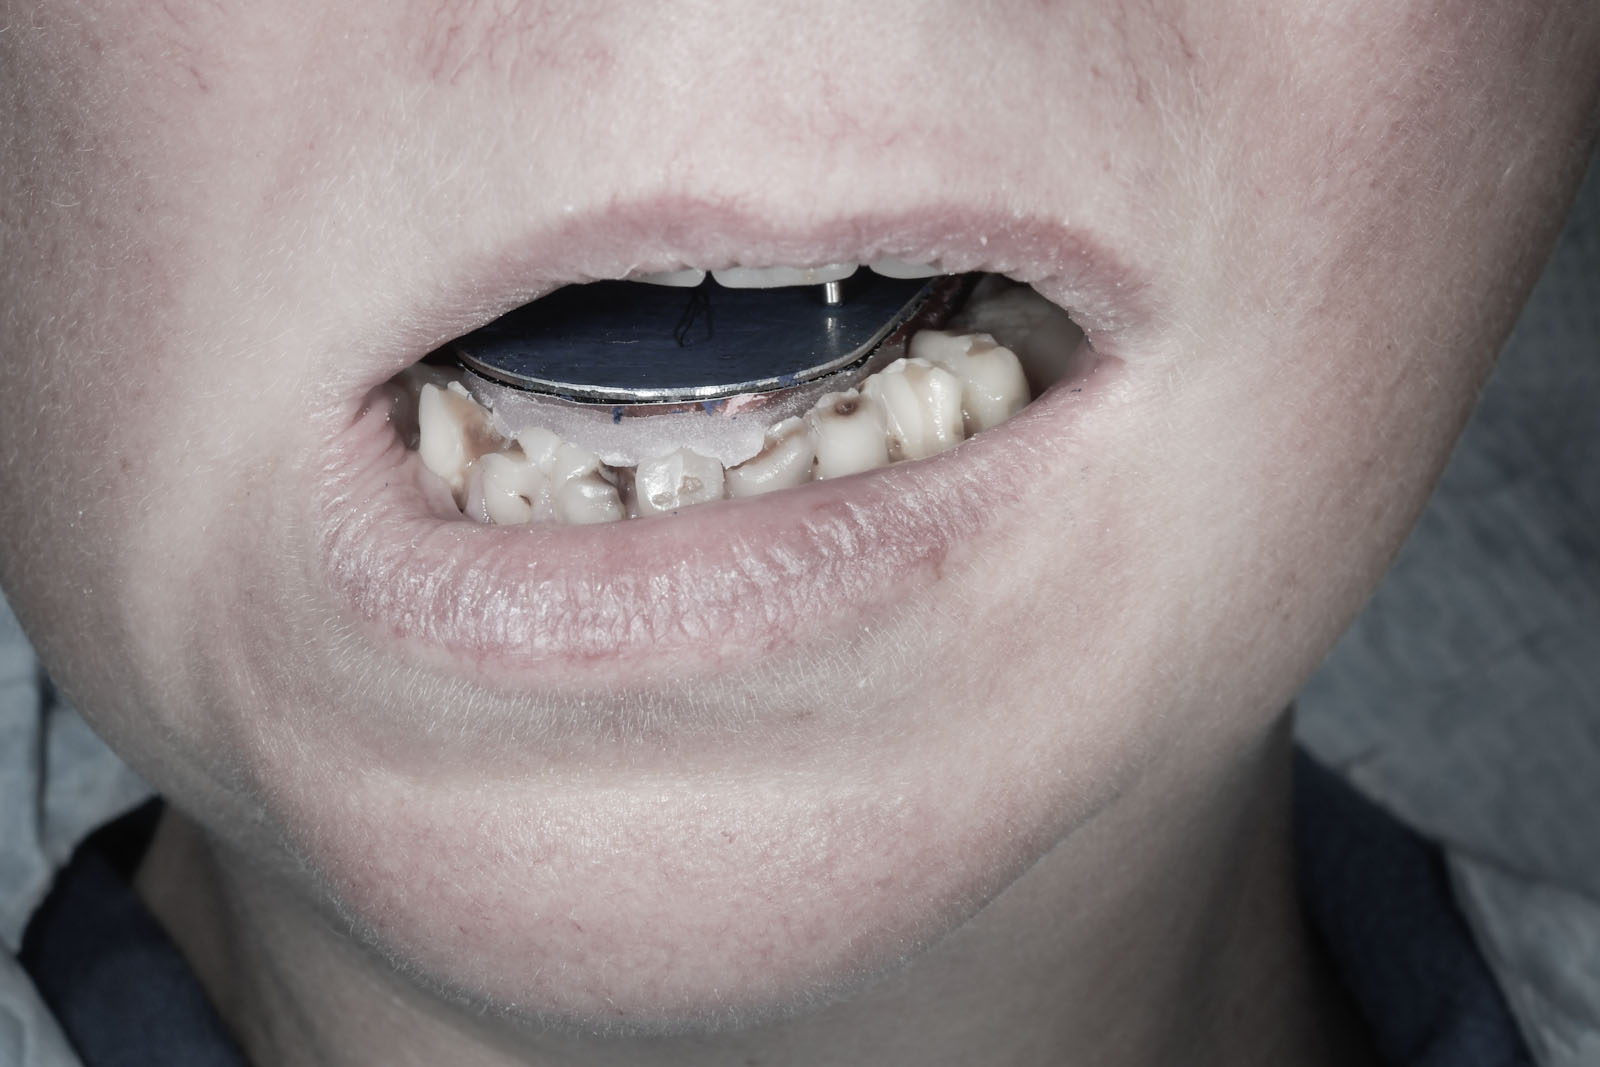

Ma zastosowanie zarówno u dzieci, jak i dorosłych. Stosowana jest u pacjentów posiadających pełne uzębienie, którzy wymagają przywrócenia jego funkcji lub jedynie korekty estetyki, a także u pacjentów z częściowymi brakami w uzębieniu. Jest szczególnie pomocna przy bezzębiu.

W pierwszym etapie wykonuje się modele robocze, które są montowane w opracowanym przez prof. Gerbera artykulatorze. Tak zwany condylator pozwala na symulację trójwymiarowych ruchów głów żuchwy. Pozwala na zweryfikowanie poprawności relacji pomiędzy łukiem zębowym górnym a dolnym. Po dokładnym zbadaniu funkcji i morfologii stawu sż, wykonaniu pomiarów oraz ocenie stanu zdrowia zębów zostaje opracowany indywidualny plan leczenia zgodny z uwarunkowaniami pacjenta.

Dzięki zastosowaniu łuku twarzowego możliwy jest pomiar kątów nachylenia torów przesuwania głów żuchwy. Pozwala to na zamontowanie modeli gipsowych w stosunku do stawów skroniowo-żuchwowych i płaszczyzny Campera (linii uszno-nosowej) orientacyjnej w widoku z profilu. Ma to na celu odtworzenie prawidłowej okluzji, czyli odpowiedniej pozycji stykania się zębów górnych z dolnymi.